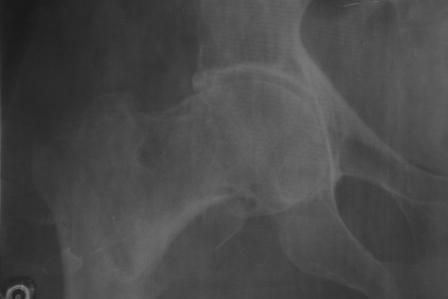

Доставлена   больная   72  года.  3  дня  назад  упала.  На   R-грамме

чрезвертельный  простой АО 31А1  перелом   левой  бедренной   кости.

Кроме  того  имеется  подозрение  на  субкапитальный  31В1  перелом ,  у

меня  на  практике  такое  впервые.  Трижды  сделали  R-графию,  но

качественный  снимок  не  получилось. КТ  в  диагностическом   центре

на  ремонте.

1.  Действительно ли  имеется субкапитальный   перелом,  или  мне

так  кажется?

2.  Если  да,  то   что   можно  делать?   В  наличии  имеются

длинные  спонгиозные  винты,  большие  расширяюшиеся  в  конце  винты

ЦИТО,  Г- образные  и  продольные  пластини  АО,  пластина

Троценко-Нуждина,  и  мыщелковые   пластины, заимствованные  у  Джолдаса.